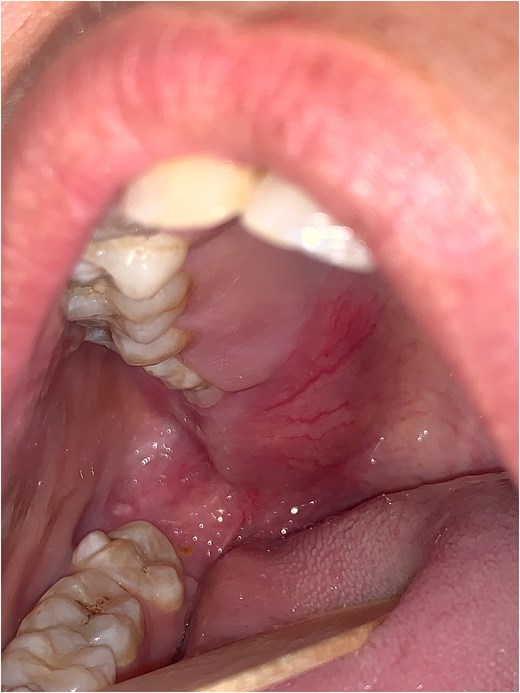

A 23-year-old female patient with no medical history presented with gingival swelling of the retromaxillary and palatal gingiva that appeared two months prior and gradually increased in size. She reported no pain, teeth mobility, restriction of mouth opening, or numbness. Physical examination revealed a well-rounded red swelling of the right retromaxillary gingiva with telangiectasias, measuring approximately 1 cm in diameter, soft, and nontender. Mouth opening, sensitivity, and motility were normal. No lymph nodes were palpable, and the general examination was unremarkable (Fig. 1).